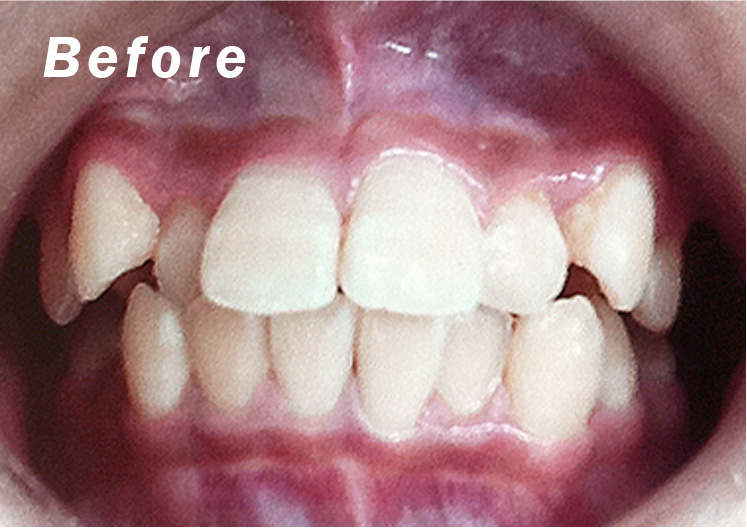

• 症例1

矯正bofore

矯正after

矯正種類 マウスピース矯正

症例 すきっ歯

治療期間 令和5年9月〜令和6年3月 6ヶ月

性別/年代 男性/20歳9ヶ月

治療費 上下顎 : 280,000円(税別)

短期間でしっかり空隙も無くなりました。

上顎だけの治療でしたが、その過程で下顎の叢生(でこぼこ)も綺麗になった好症例です。